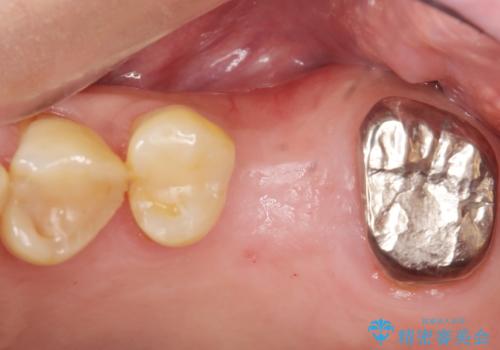

奥歯のインプラント ソケットリフト 60代男性

- 奥歯のインプラントをご希望し、来院された患者様です。

精査したところ上顎骨の厚みが薄かったため、ソケットリフト(上顎洞底挙上術)を併用してインプラント治療を行いました。